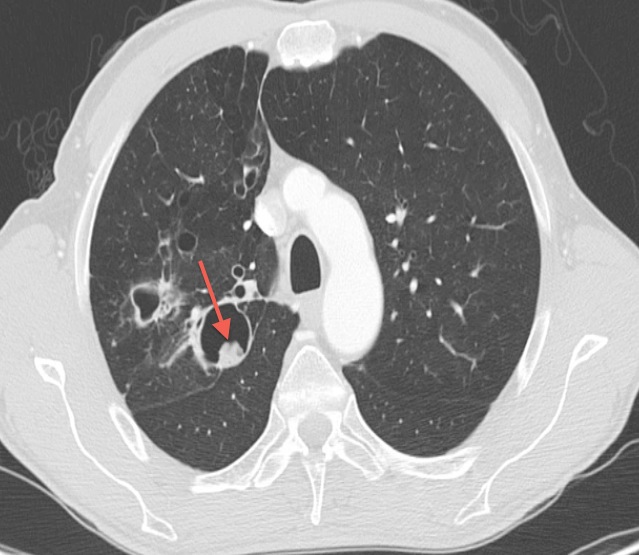

Визуализация и диагностика неинвазивного аспергиллеза с помощью КТ

Раздел: Необычные решения